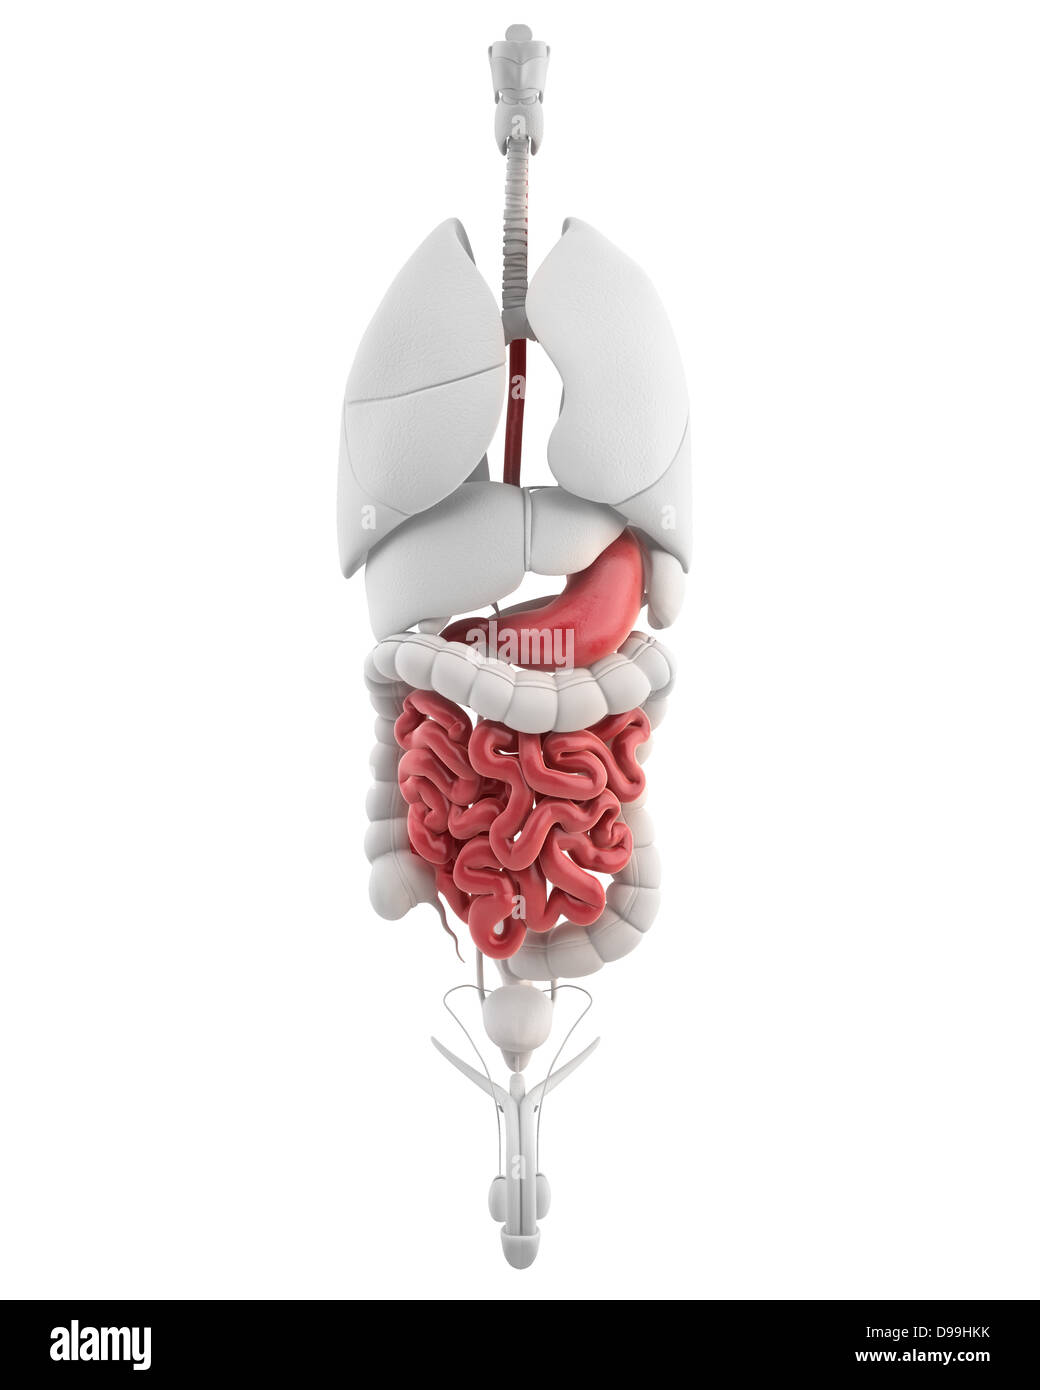

RFDGYRD7–Männliche Anatomie, inneren Organe allein, volle Atmungs- und Verdauungssystem, mit einigen Organen Cutaway. Anatomie-Bild.